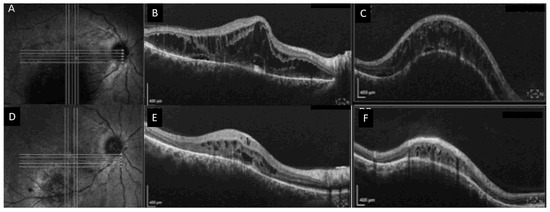

3. Case Number 2